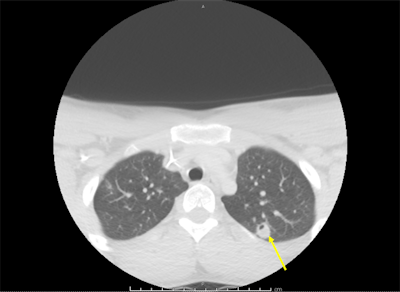

Though the initial CTA failed to show pulmonary emboli, a subsequent CT scan showed evolving cavitation of the multiple nodular densities seen on the initial chest x-ray. The findings were consistent with septic pulmonary emboli. A vascular surgeon recommended that the teen's condition be managed without surgery.

The patient improved and was discharged after 12 days at the hospital. A CT scan was completed again at follow-up, which showed the jaw had a periosteal reaction. He was treated with six weeks of the antibiotic ertapenem. One month after discharge, imaging showed that the pulmonary infiltration and superficial internal jugular vein thrombosis had resolved, and the left mandibular osteomyelitis had improved.